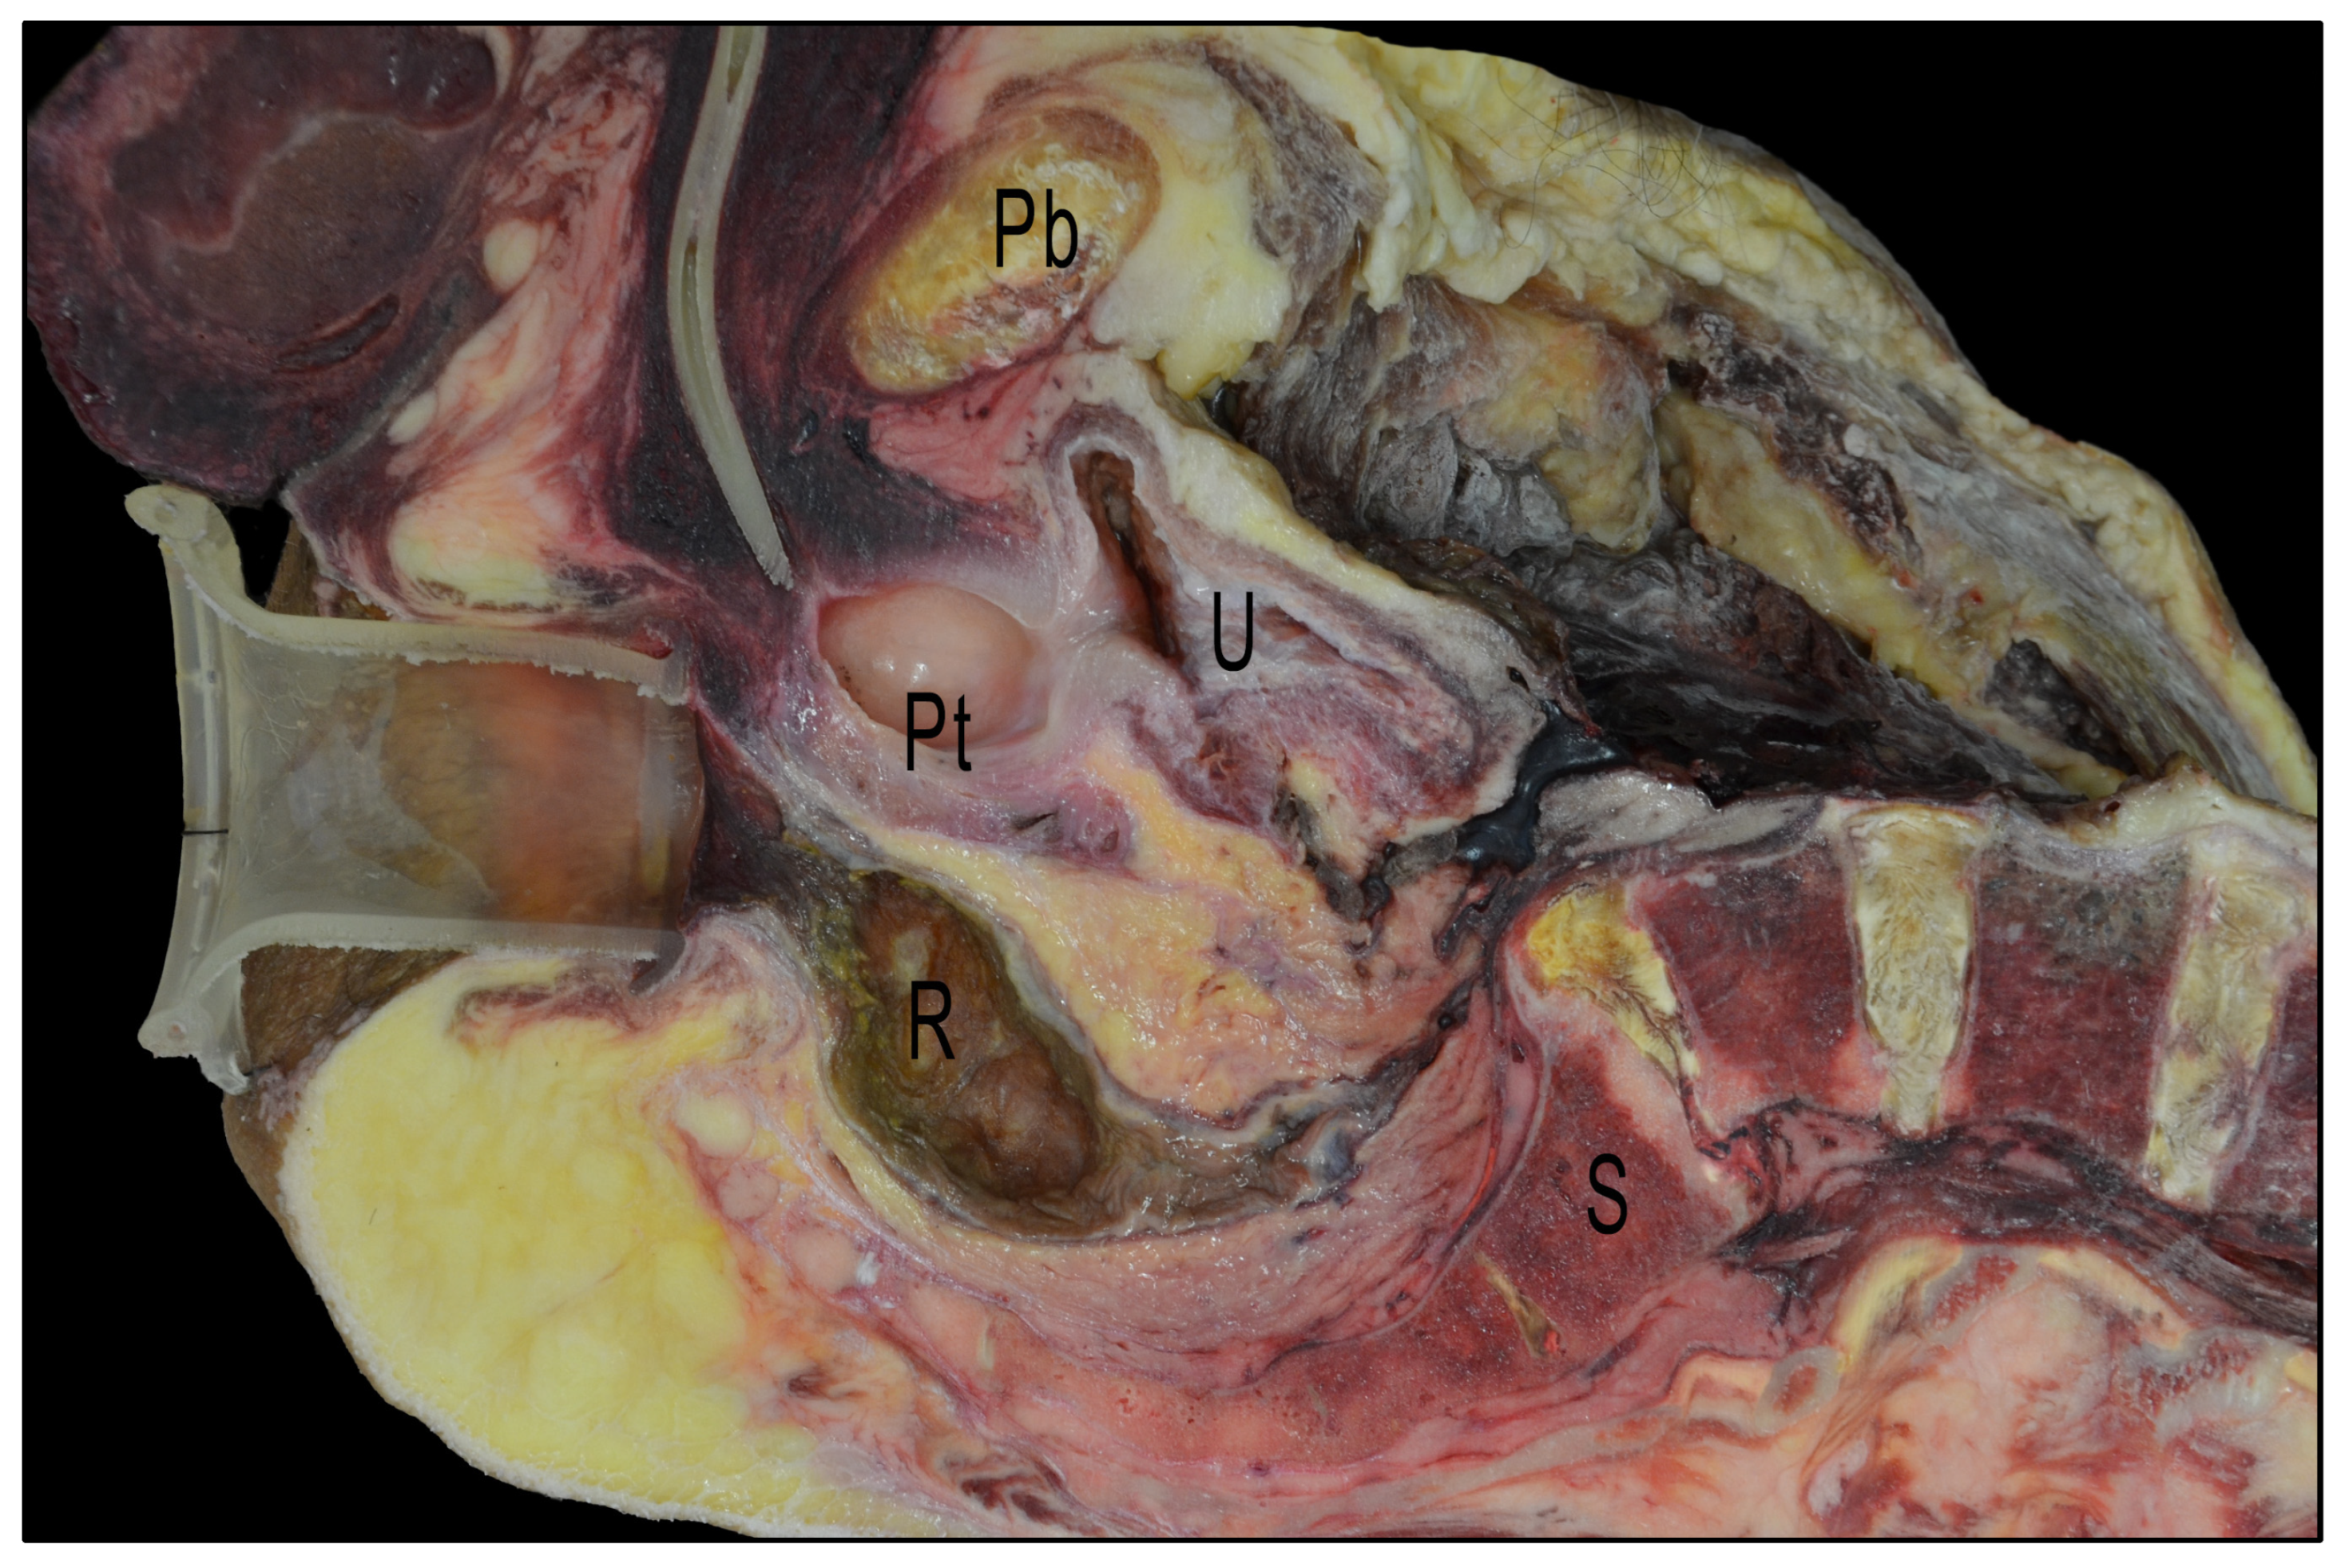

2.3. Cadaveric Dissection

- The shortest distance between the anterior surface of the rectum and the membranous urethra (R-Mu distance);

- The distance between the point on the anterior wall of the rectum closest to the membranous urethra and the anal margin (R-Am distance);

- The angle formed by the intersection of the axis of the anal canal and the axis of the rectum (anorectal angle).

3.1. Cadaveric Dissection